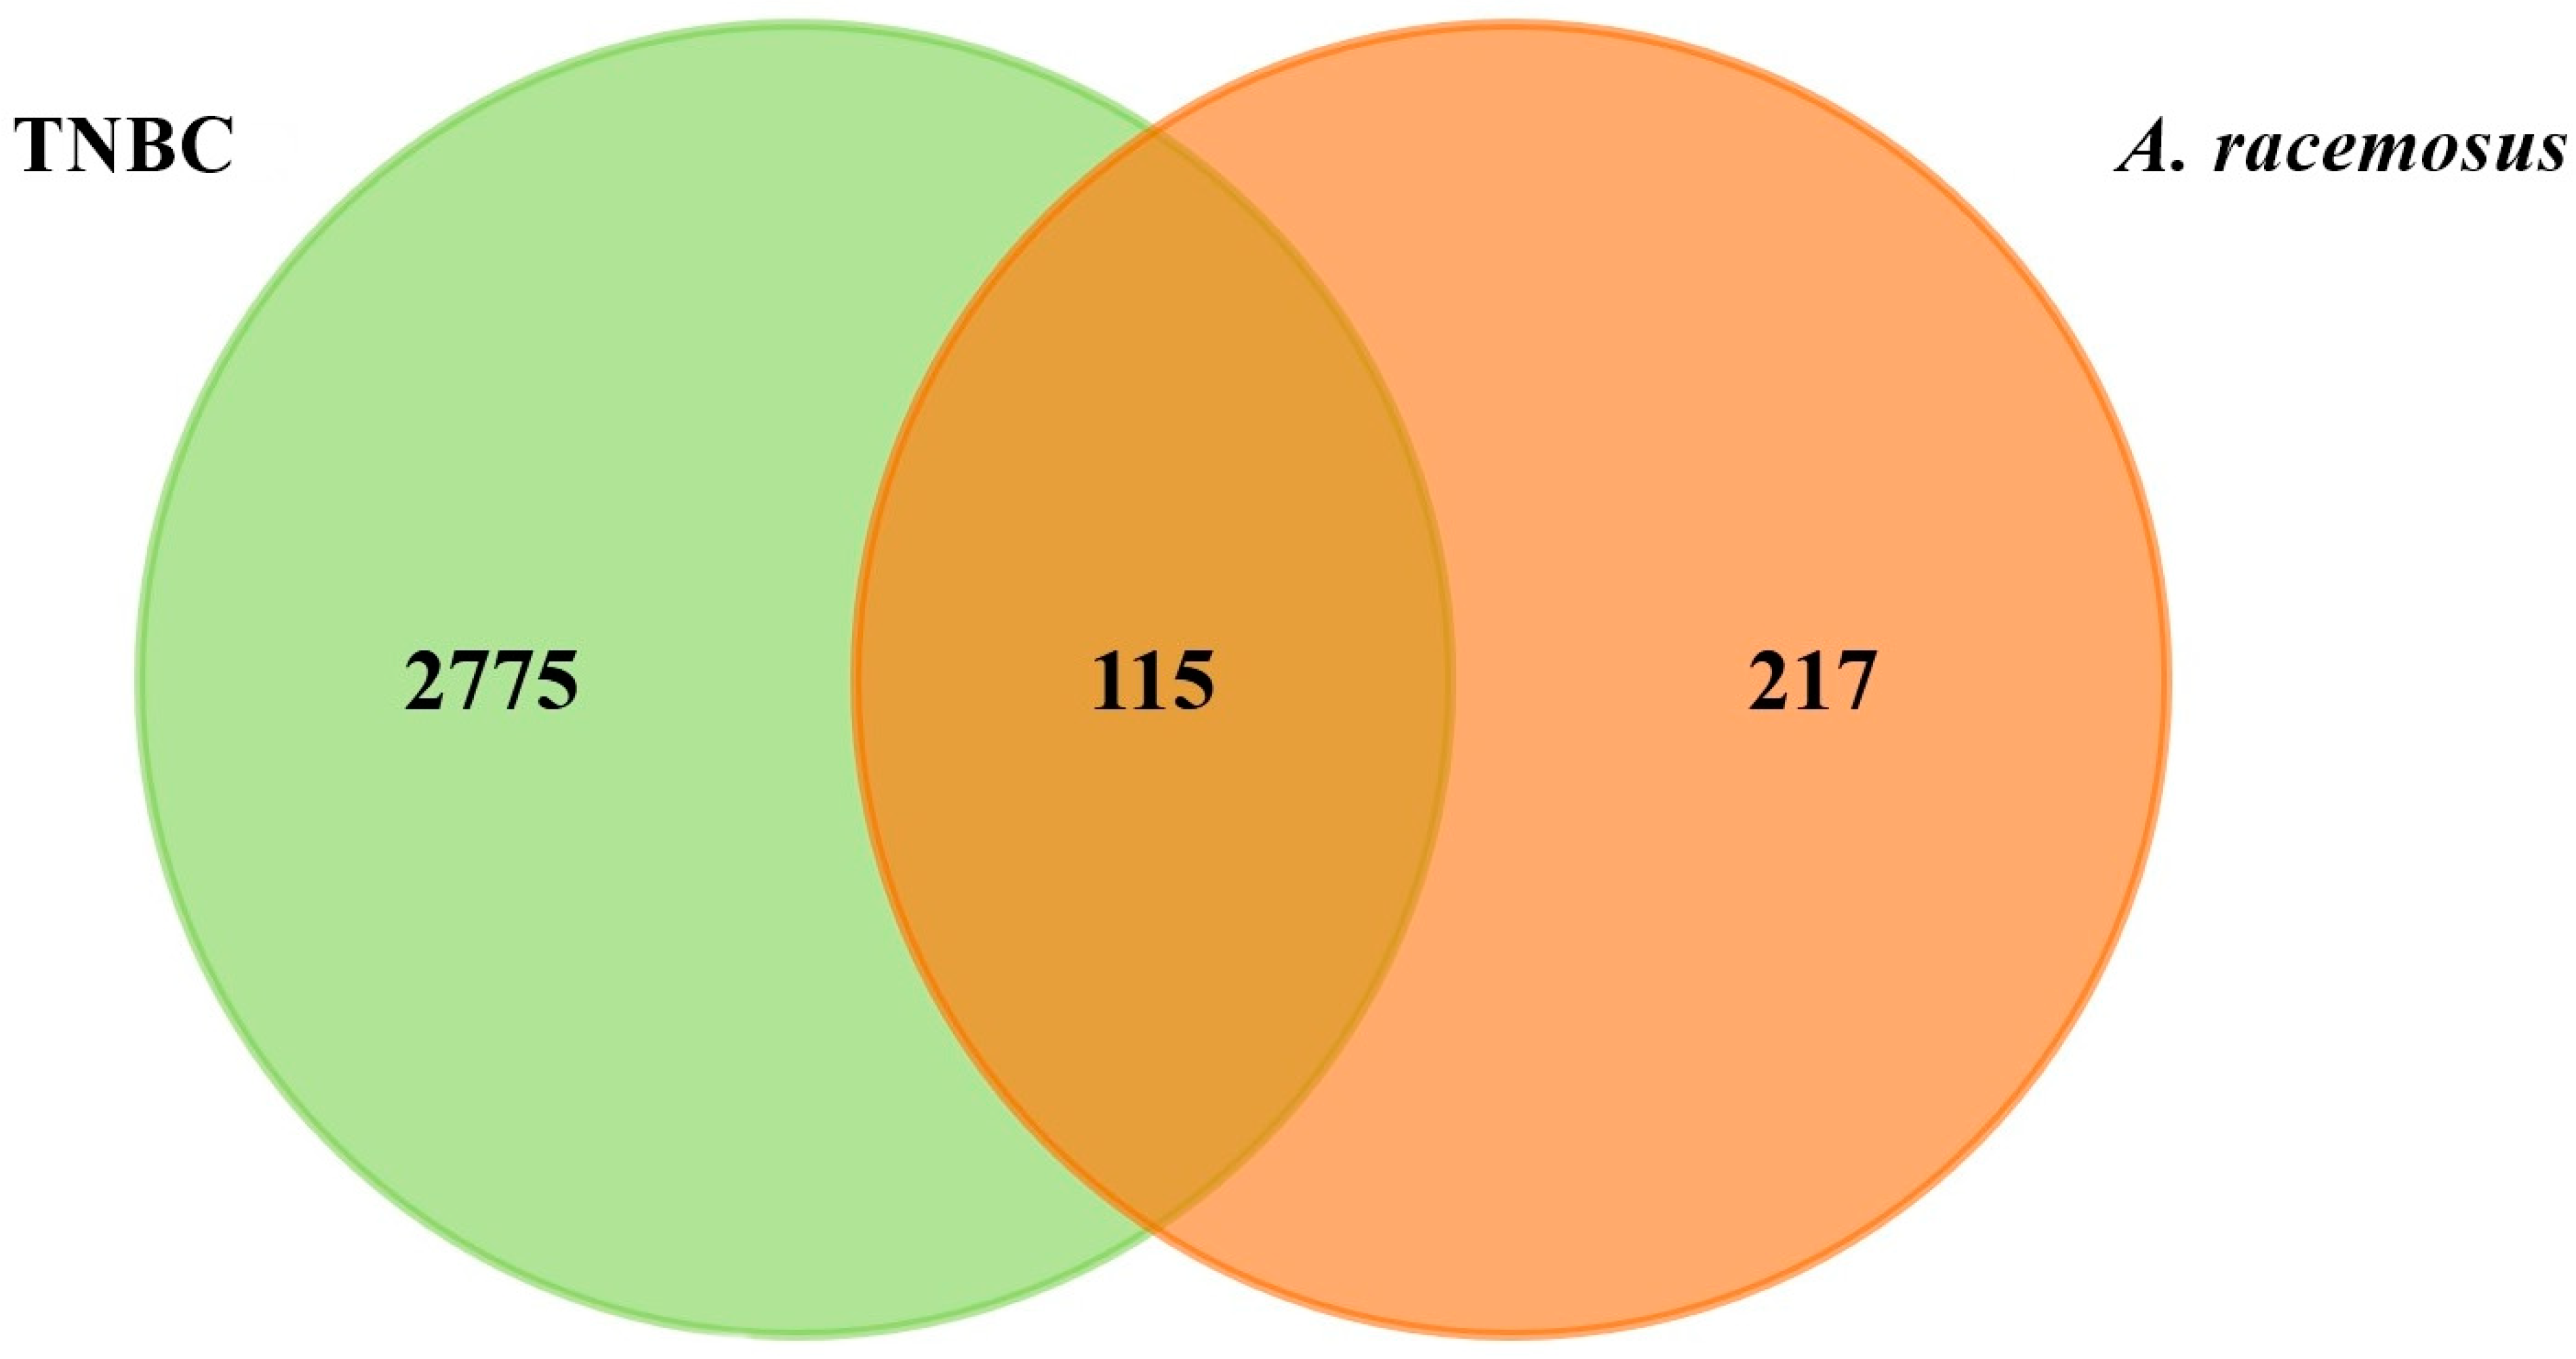

2.2. Prediction of Targets and Screening for Potential Targets

2.3. Identifying Hub Genes and Construction of Compounds-Disease Common Target Network